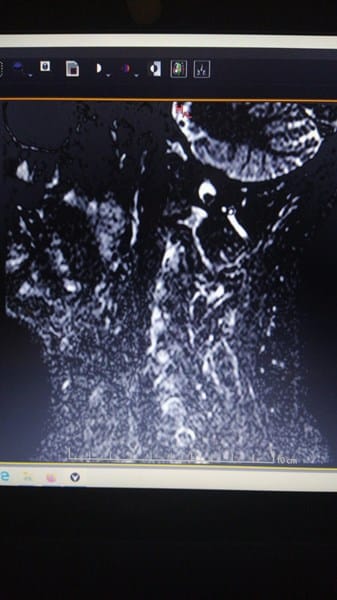

2/ Resonancia Magnética

Adjunto fotografias de la resonancia.